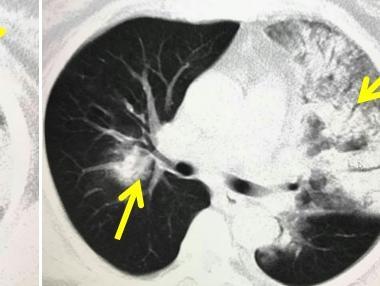

肺部感染ct图片

肺部感染ct

严重肺部感染ct图片

肺部感染ct图片怎么看

肺部感染的ct影像图片